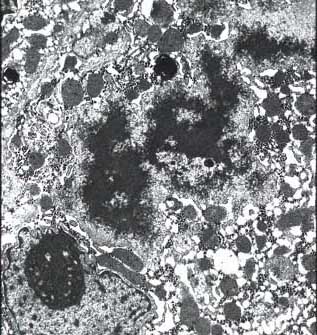

Phospholipidosis: there are foamy hepatocytes plus, under electron microscopy, large lysosomal inclusions composed of densely packed concentric membranes with a fingerprinting pattern. There is also reduction of the crystae in the mithochondria and vesicles in the smooth ER. The lesion was recognized by Oda in Japan in 1969. Later, in 1975, it was recognized by Lullman et al in inborn errors of phospholipid metabolism. Drugs responsible: Colargil (Oda et al. 1969), Amiodarone (Pousell et al.1984).

8-4-4.jpg (72265 bytes)

Fig. 8-4-4 Amiodarone hepatitis

54 year old male taking amiodarone for many years developed clinical hepatitis: ALT 780, AST 339. This slide demonstrates hydropic swelling of hepatocytes, focal cell necrosis with inflammatory reaction and cytoplasmic cholestasis. TheReview of Pathology of the Liver:Table of Contents foamy appearance is due to phospholipidosis present practically in every case  and is due to accumulation of

sphingomyelin in hepatocytes. (see Em Picture below).